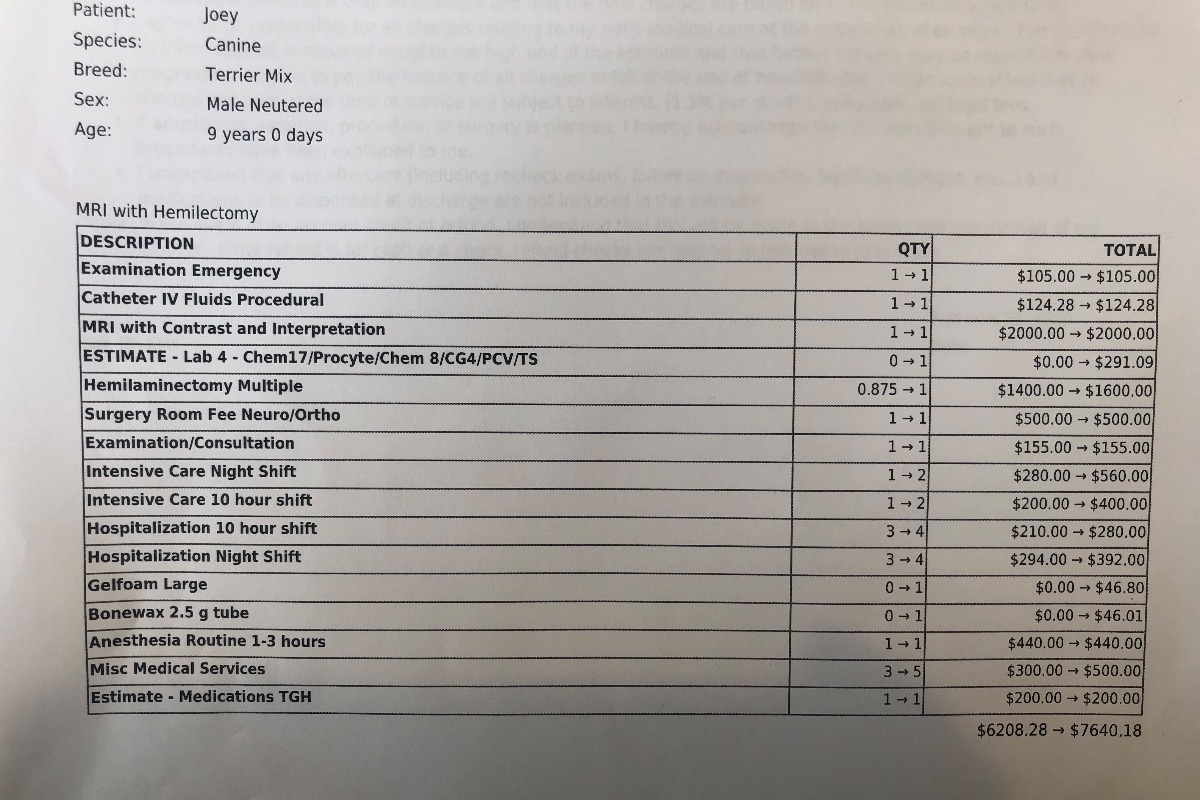

Surgery & Post-Op

Surgery is a bit more complicated due to the nature of the case. It will take 3-4 hours. Joey will be hospitalized for 3-4 days. Recovery will take one month of full bed rest.

The vet bills are no joke

Animal hospital vet visit for neuro consult + emergency surgery

Animal hospital vet visit for neuro consult + emergency surgery

Surgery & Post-Op

Surgery is a bit more complicated due to the nature of the case. It will take 3-4 hours. Joey will be hospitalized for 3-4 days. Recovery will take one month of full bed rest.

The vet bills are no joke

Animal hospital vet visit for neuro consult + emergency surgery

Animal hospital vet visit for neuro consult + emergency surgery